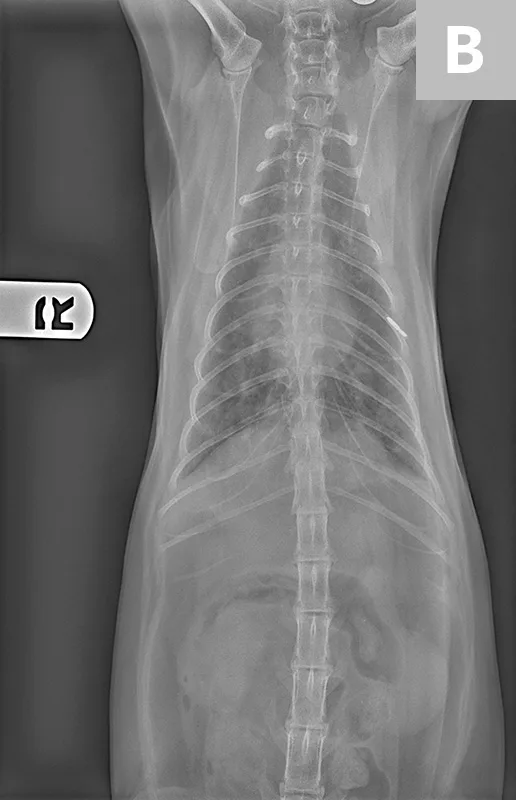

Radiographs of the thorax revealed a diffuse, finely granular interstitial pulmonary infiltrate with prominent bronchial markings with indistinct nodules in the middle and caudal lung lobes (Figure 2).

Figure 2

Diffuse, finely granular interstitial pulmonary infiltrate (A) with prominent bronchial markings with indistinct nodules in the middle and caudal lung lobes (B)